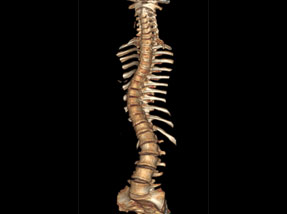

• Post Surgery

• Post SurgeryAfter

Case 1